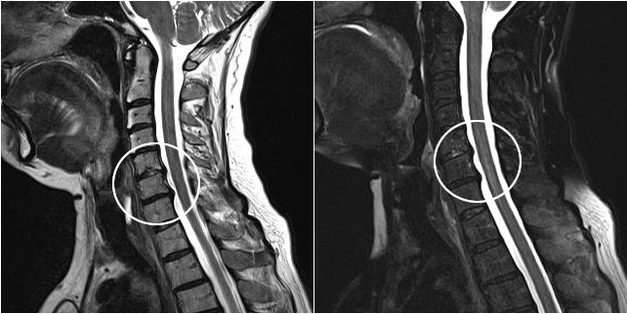

Los métodos de diagnóstico modernos incluyen MRI y CT, que permiten examinar con mayor precisión los procesos de destrucción del cartílago y el tejido óseo. Además, mediante esta técnica es conveniente diagnosticar hernias y otros defectos de tejidos blandos cercanos al origen de la enfermedad.